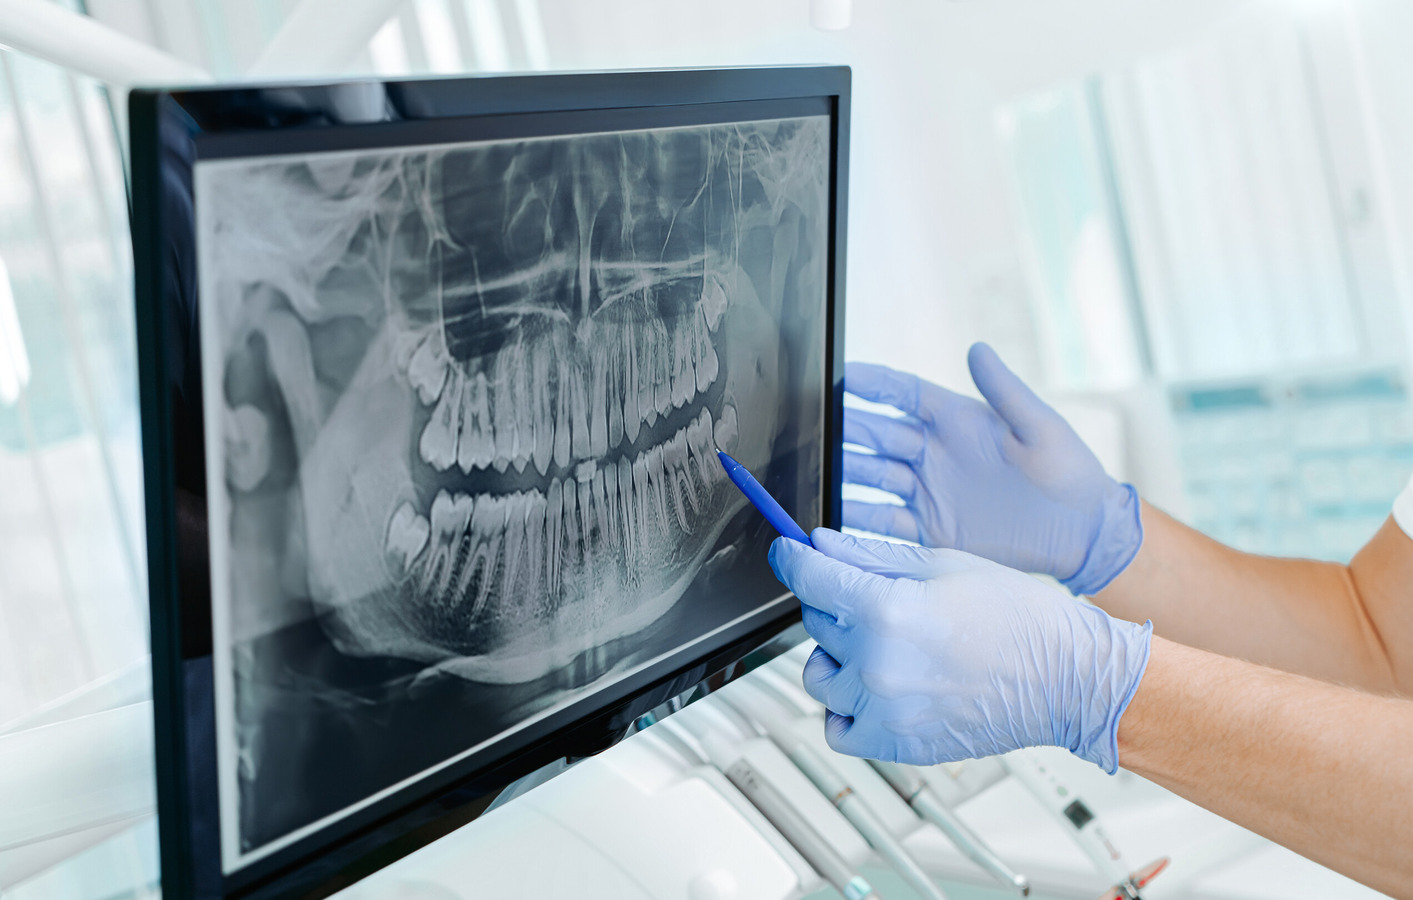

Dental X-rays are essential for orthodontics because they let the dentist see what is going on beneath the surface of your teeth and gums that a simple visual examination or even a 3D scan cannot reveal. Specifically, X-rays help orthodontists:

Assess tooth position and development: X-rays show the exact alignment of teeth, root development, and whether any teeth are impacted (stuck under the gums) or coming in at unusual angles.

Evaluate the growth and structure of the jaw: X-rays provide insight into the bones of the jaws and face and help diagnose skeletal problems such as overbites, underbites or asymmetries that braces or other orthodontic treatments need to address.

Check for missing or extra teeth: They identify congenitally missing teeth or extra (supernumerary) teeth which can affect the growth and development of the permanent teeth. Orthodontists can also use X-rays to assess the positions of wisdom teeth and predict how they will ultimately affect treatment.

Monitor dental and root health: X-rays can detect root resorption, cysts, or other problems that may affect long-term dental health, movement, or stability during treatment.

Plan safe, effective treatment: Accurate diagnosis from x-rays helps orthodontists develop a treatment plan that minimizes complications and maximizes long-term results. This is the ultimate purpose of dental x-rays and why our orthodontists insist on them.

Dental X-rays give orthodontists the full picture needed to safely move teeth, correct bite problems, and ensure your smile remains healthy and stable for years to come.